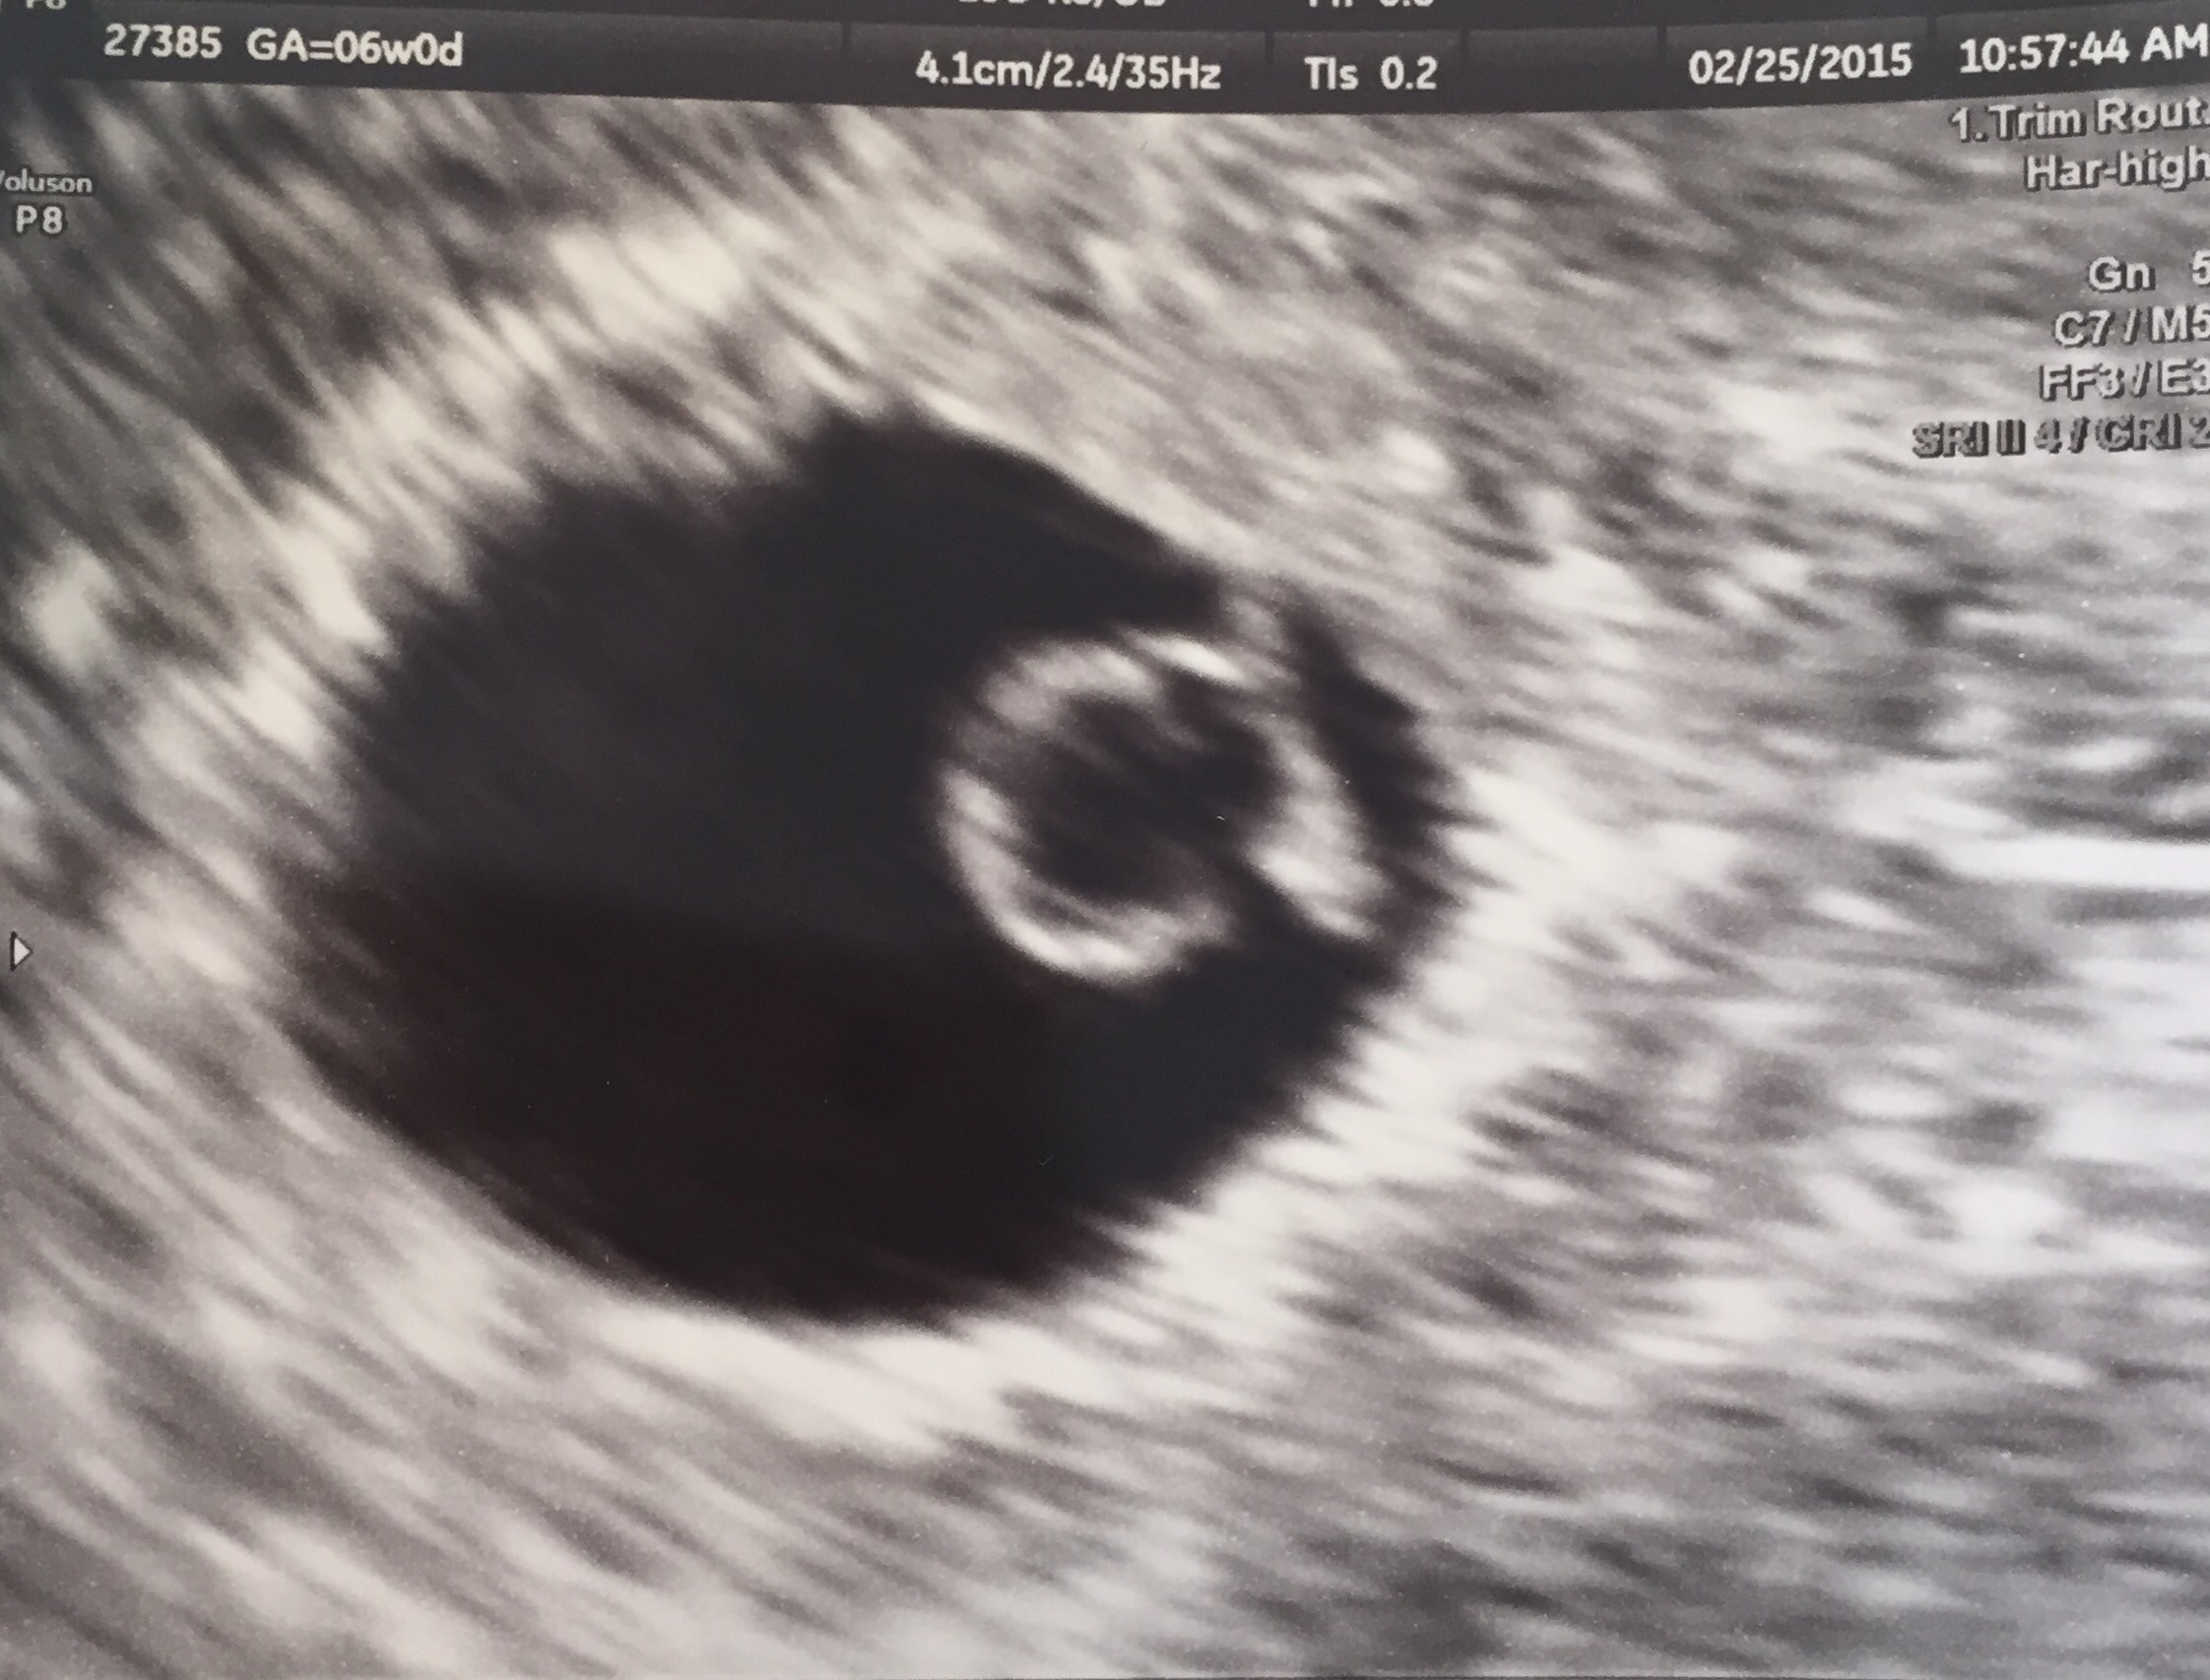

• Due the 22nd! Had my ultrasound two days ago. I have PCOS and my cycles are irregular so we went in to get a due date. My progesterone levels are super low so they put me on a supplement and injections. This is our first so it's worth it! We got to see/hear the heartbeat too!!

• Due on 10/20! Had our first us last week. Somewhere in there is a very happy little one with a perfect heartbeat :-)